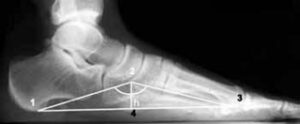

Степени плоскостопия на рентгенографии

Плоскостопие — это искривление стопы, поражение стопы, характеризующееся постоянным уменьшением высоты дистального свода стопы до тех пор, пока оно не исчезнет. Этот вид деформации наиболее распространен и может сопровождаться патологическими изменениями в коленных и голеностопных суставах. Патология диагностируется на основании прямого осмотра, а степень плоскостопия определяется на основании рентгенологического исследования. Последовательность проведения рентгенографии стопы Рентген …